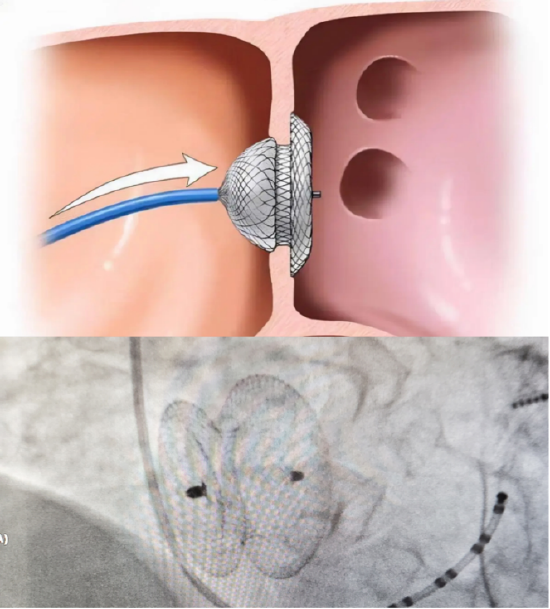

哈医大一院多学科联合一次入路完成经导管射频消融术 经皮房间隔缺损

图片尺寸550x609